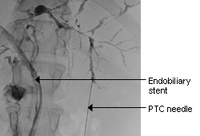

Typical endoscopic retrograde cholangiopancreatography findings in a patient with PSC: multi-focal strictures of the intra- and extrahepatic bile ducts

Dr Kris Kowdley's collection